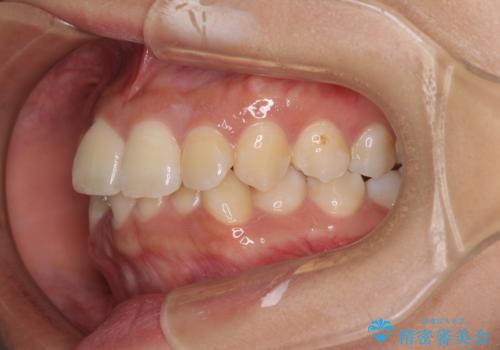

前歯のデコボコと隠れてしまう下顎前歯 インビザラインですっきりと改善

- 前歯のデコボコと、深い咬み合わせにより前歯が隠れていることを気にして来院された患者様です。

海外に長期滞在する予定があるとのことで、インビザラインにて矯正治療を行うこととしました。

インビザライン発注後に長期滞在先から2年間ほど帰国することができず、インビザラインの有効期限内に終了できるのか不安でしたが、矯正治療開始後は十分な装着時間を達成され、1年未満の期間で無事に終えることができました。